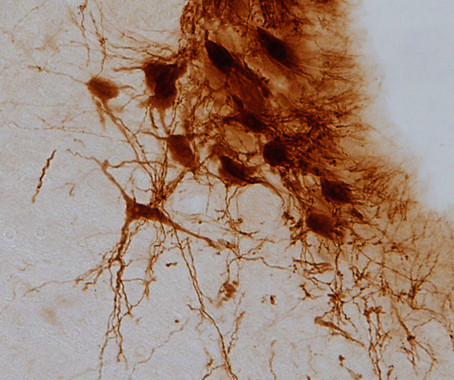

Moléculas reguladas con luz para aliviar síntomas del dolor crónico